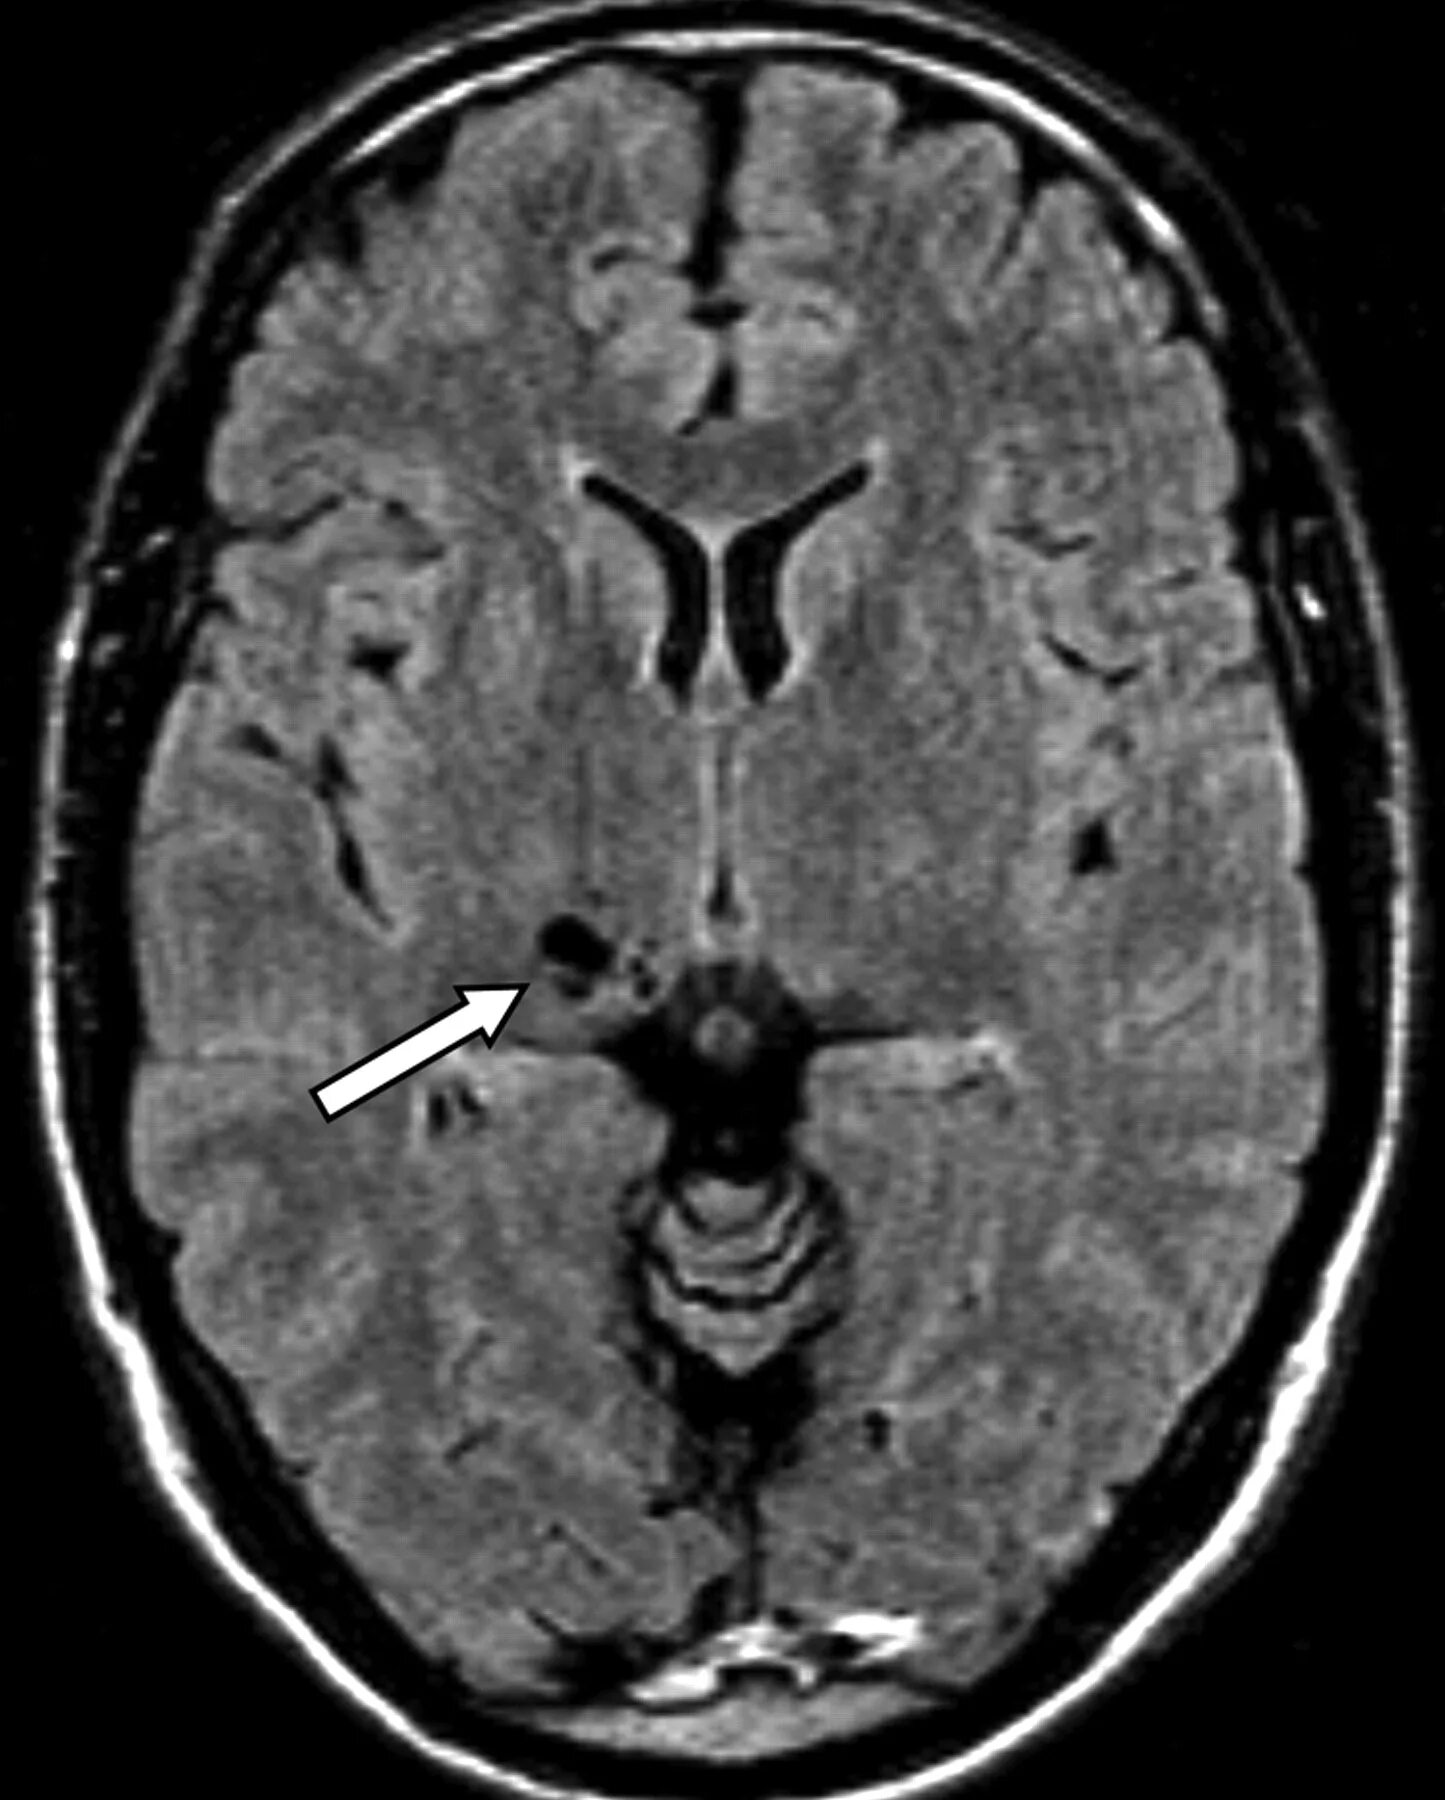

Что значит расширенные периваскулярные пространства